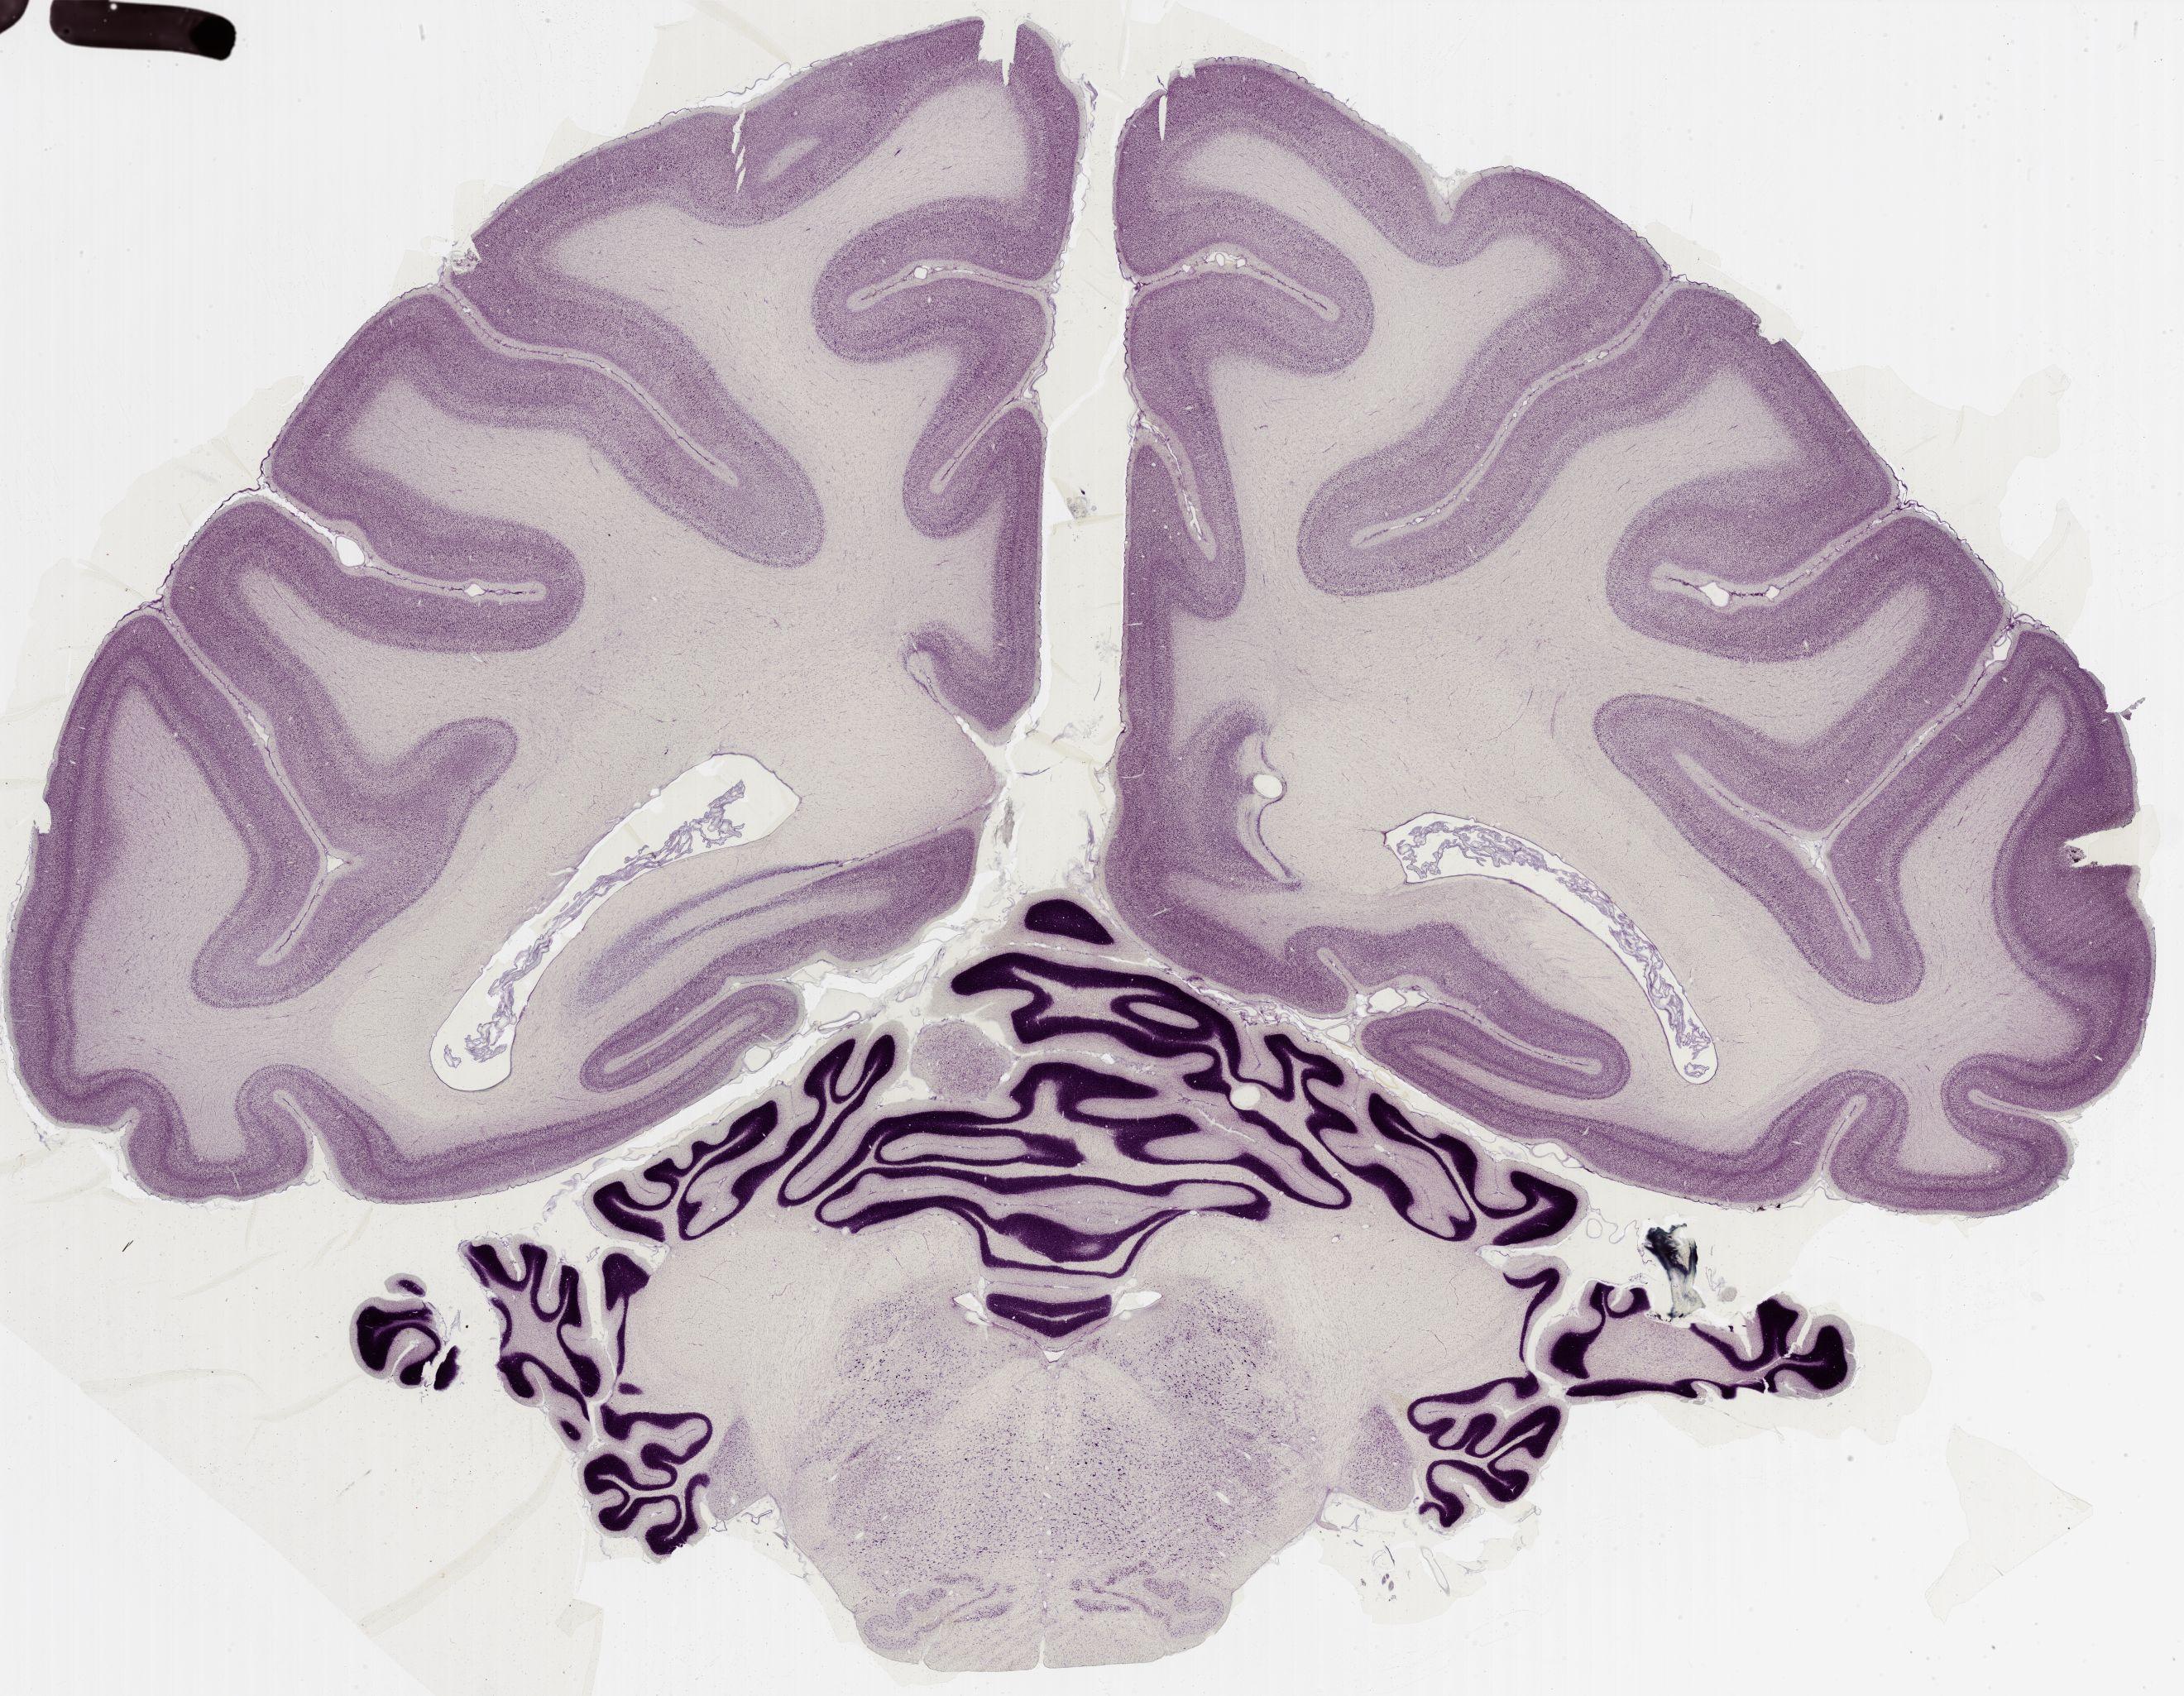

Datasets -> Macaca Mulatta -> Nissl, coronal, histo, Whole-Brain, adult

[ Metadata ]   ·   Source: Edward G. Jones

thumbnail

0565 - labeled